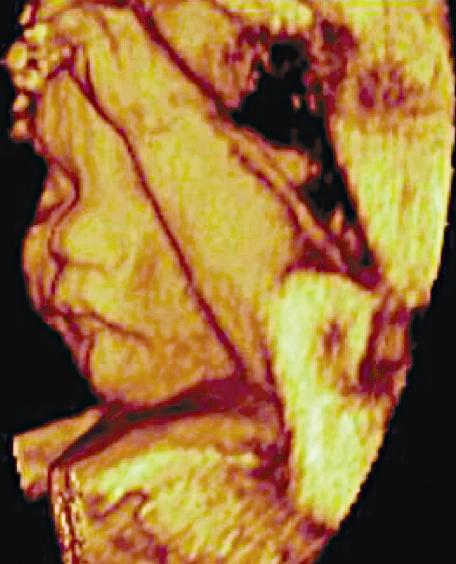

Three-Dimensional Ultrasound

Dedicated 3-D scanners used for fetal (Fig. 1.21), gynecologic, and cardiac scanning may employ hardware-based image registration, high-density 2-D arrays, or software registration of scan planes as a tissue volume is acquired. 3-D imaging permits volume

data to be viewed in multiple imaging planes and allows accurate measurement of lesion volume.

FIG. 1.21 Three-Dimensional Ultrasound Image, 24-Week Fetus. Three-dimensional ultrasound permits collection and review of data obtained from a volume of tissue in multiple imaging planes, as well as a rendering of surface features.